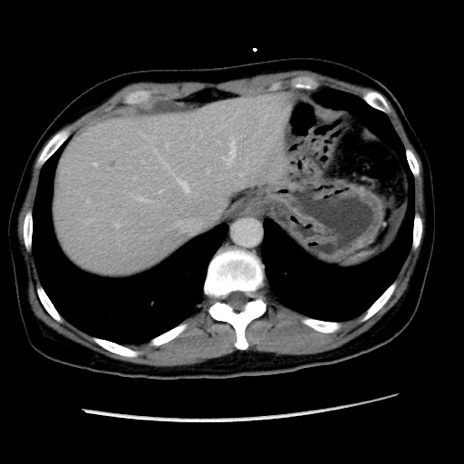

症例10(横断像)

【症例】 50歳代女性

【主訴】 腹痛

【現病歴】前日生レバーを食べた。今朝に排便あり。 昼前に突然発症の腹痛を生じ、当院救急外来を受診した。

【既往歴】 子宮筋腫にてで子宮全摘後

【身体所見】 意識清明、腹部:平坦、軟、下腹部やや左を中心に圧痛・反跳痛あり、筋性防御あり

【データ】WBC 7800、CRP 0.07